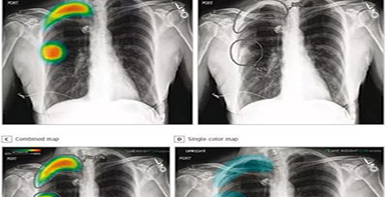

Unlike other AI tools currently on the market, ARIES uses a holistic model that analyzes the entire X-ray or CT scan (Figure 1). It then generates a personalized report that is 95% complete. It summarizes the findings in the radiologist’s reporting style and offers a template to augment the radiologist’s diagnosis and treatment. The system also flags life-threatening conditions in real time.

Figure 1: ARIES generates a report using an image and input, allowing radiologists to review in a timelier manner.